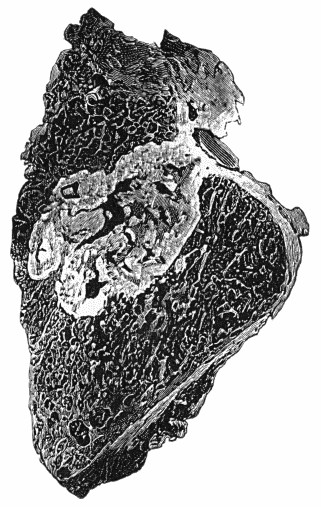

313 75.Innominate Aneurysm in a woman

315 76.Congenital Cystic Tumour or Hygroma of Axilla